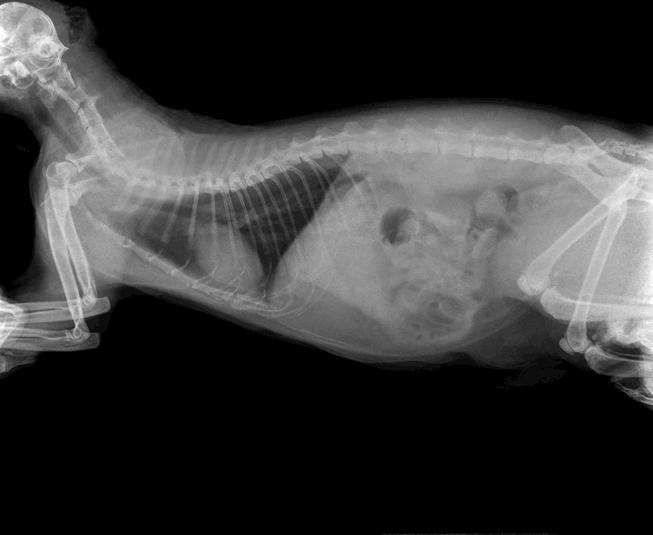

Se pueden solicitar diagnósticos visuales, que incluyen radiografías o ecografías, y es probable que se realice una endoscopia. Además de proporcionar una imagen visual de los intestinos, también se puede usar un endoscopio para extraer muestras de tejido para biopsia y/o para extraer cuerpos extraños que se hayan ingerido.